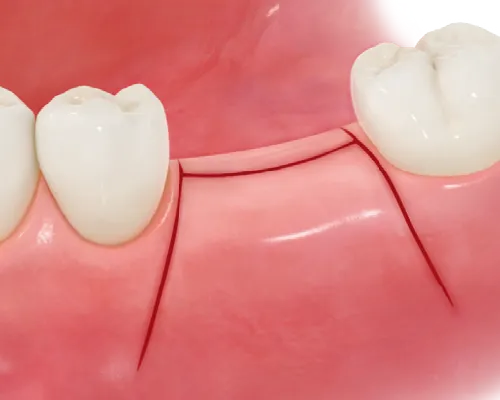

- ⑥上部構造装着(被せ物完成)

二次手術の後、歯肉の状態が安定していることを確認して型取りを行います。

型取りをした後にセラミックの被せ物が完成しますので装着します。